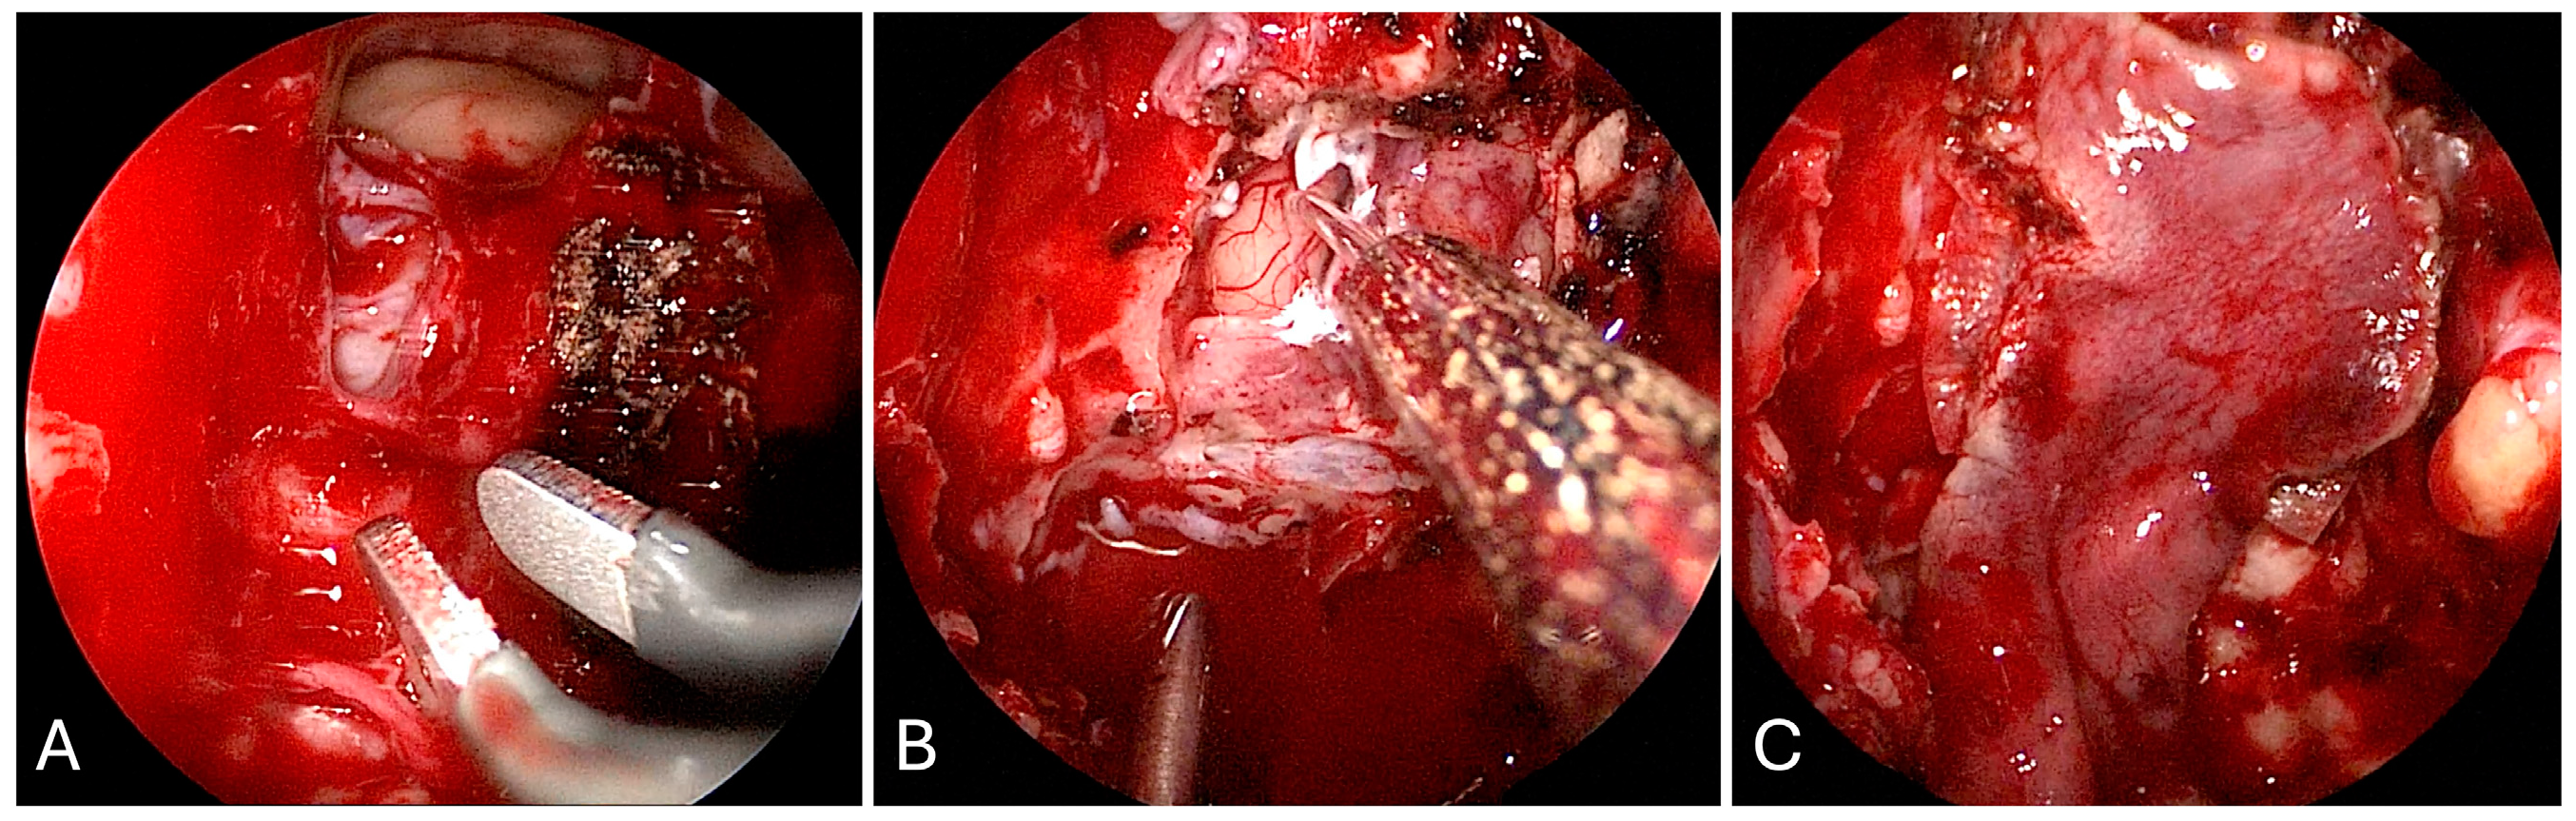

3.1.2. Illustrative Case

3.1.3. Practical Pearls

- An understanding of the osseous anatomy of the nasal corridor, paranasal sinuses, septum, intersinus septations, and relevant vascular structures are of paramount importance in the approach to sellar lesions.

- A pedicled nasoseptal rescue flap may be useful to obtain during the approach to the sellar lesions, particularly in cases of possible CSF leak, and should take into account the horizontal orientation of the posterior septal branch of the sphenopalatine artery.

- Dural opening of Rathke’s cleft cysts, one should begin anteriorly and inferiorly to minimize the risk of inadvertent CSF leak and iatrogenic injury to the pituitary gland.

- One must be mindful of diaphragm downward migration and identification during cyst resection to avoid a CSF leak.